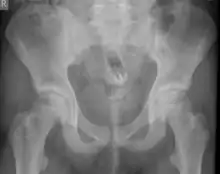

Обычно делают несколько рентгеновских снимков, чтобы точно определить место нахождения инородного тела. Инородные тела из малоконтрастного материала (например, пластика) могут потребовать ультразвукового исследования или компьютерной томографии.[28] Магнитно-резонансная томография противопоказана, особенно если неизвестен материал инородного тела. Инородные тела прямой кишки могут проникать глубоко в толстую кишку, при определенных обстоятельствах вплоть до правого изгиба ободочной кишки.[9]